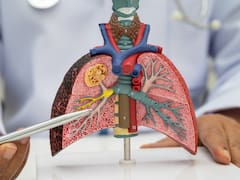

Suelen utilizar esta tecnología para realizar exámenes de a pacientes con cáncer o para planificar cirugías.

Las áreas en amarillo muestran la rápida propagación de la infección y la inflamación en ambos pulmones. La inflamación ocurre cuando el cuerpo intenta controlar la infección, causando falta de aire al paciente.